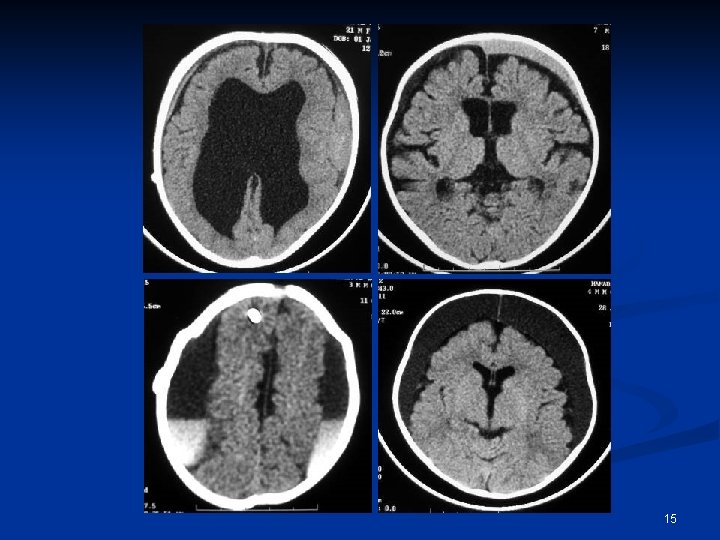

15

n n n SDH IVH SAH Pneumocephal us Edema 52